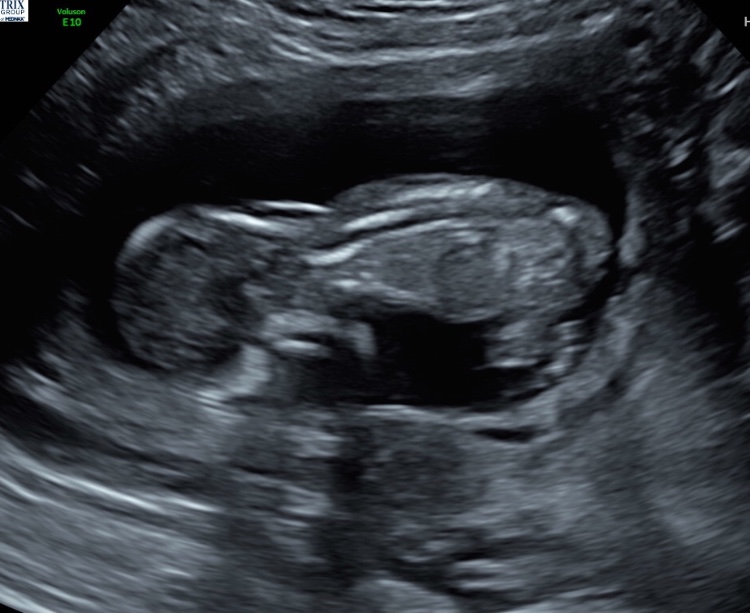

Girl or Boy? I can't tell either way...

14 weeks: